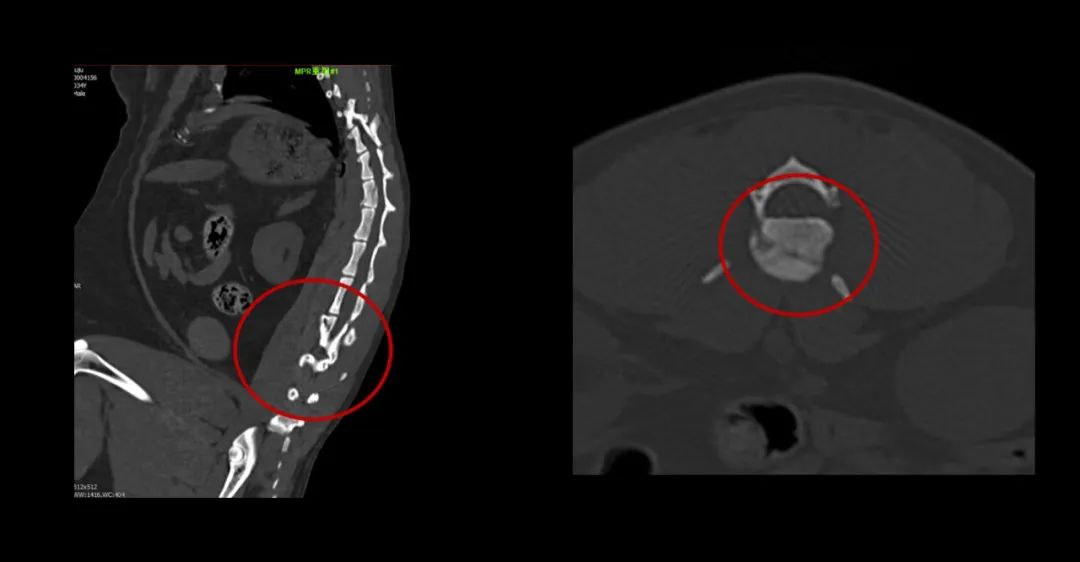

▲俗話說“貓有九條命”,可不能當真哦。你看看這兩個小家伙從樓上高空落地,一只左側股骨遠端骨折,另一只第1腰椎椎體骨折。